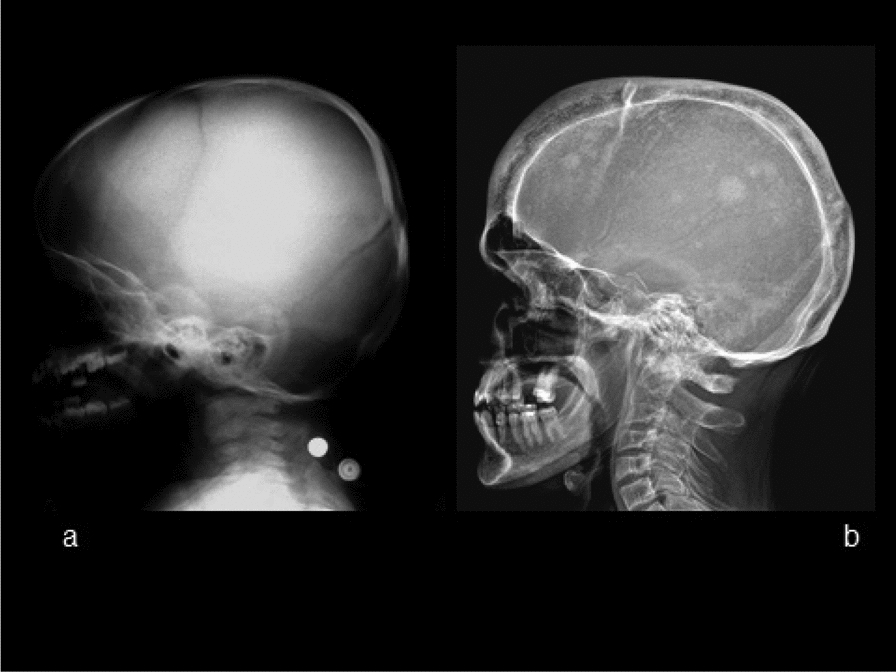

Methods and results: We report the first case of JPD diagnosed in the Czech Republic, who presented with a mild phenotype of this disease. The first bone fractures, appeared at 3 years of age. Other clinical manifestations included typical skeletal deformities, macrocephaly, arched chest, lower extremity valgosity, lateral bowing of the thighs, and anterior bowing of the shins. Minor mixed hearing impairment, angioid stripes of the choroidea, and temporary immunodeficiency were present among extra-skeletal findings. Sanger sequencing was performed on both the patient and the parents to test for the presence of TNFRSF11B sequence variants. Molecular genetic analysis showed unique compound heterozygous sequence variants in TNFRSF11B: a paternally inherited variant c.30 + 5G > A, p.(?) and a maternally inherited variant c.329G > T, p.(Gly110Val). Both of the variants were analyzed by several in silico predictive tools indicating, for their strongly supported pathogenicity according to American College of Medical Genetics and Genomics standards. Furthermore, we present diagnostic findings, their treatment, and follow-up care.